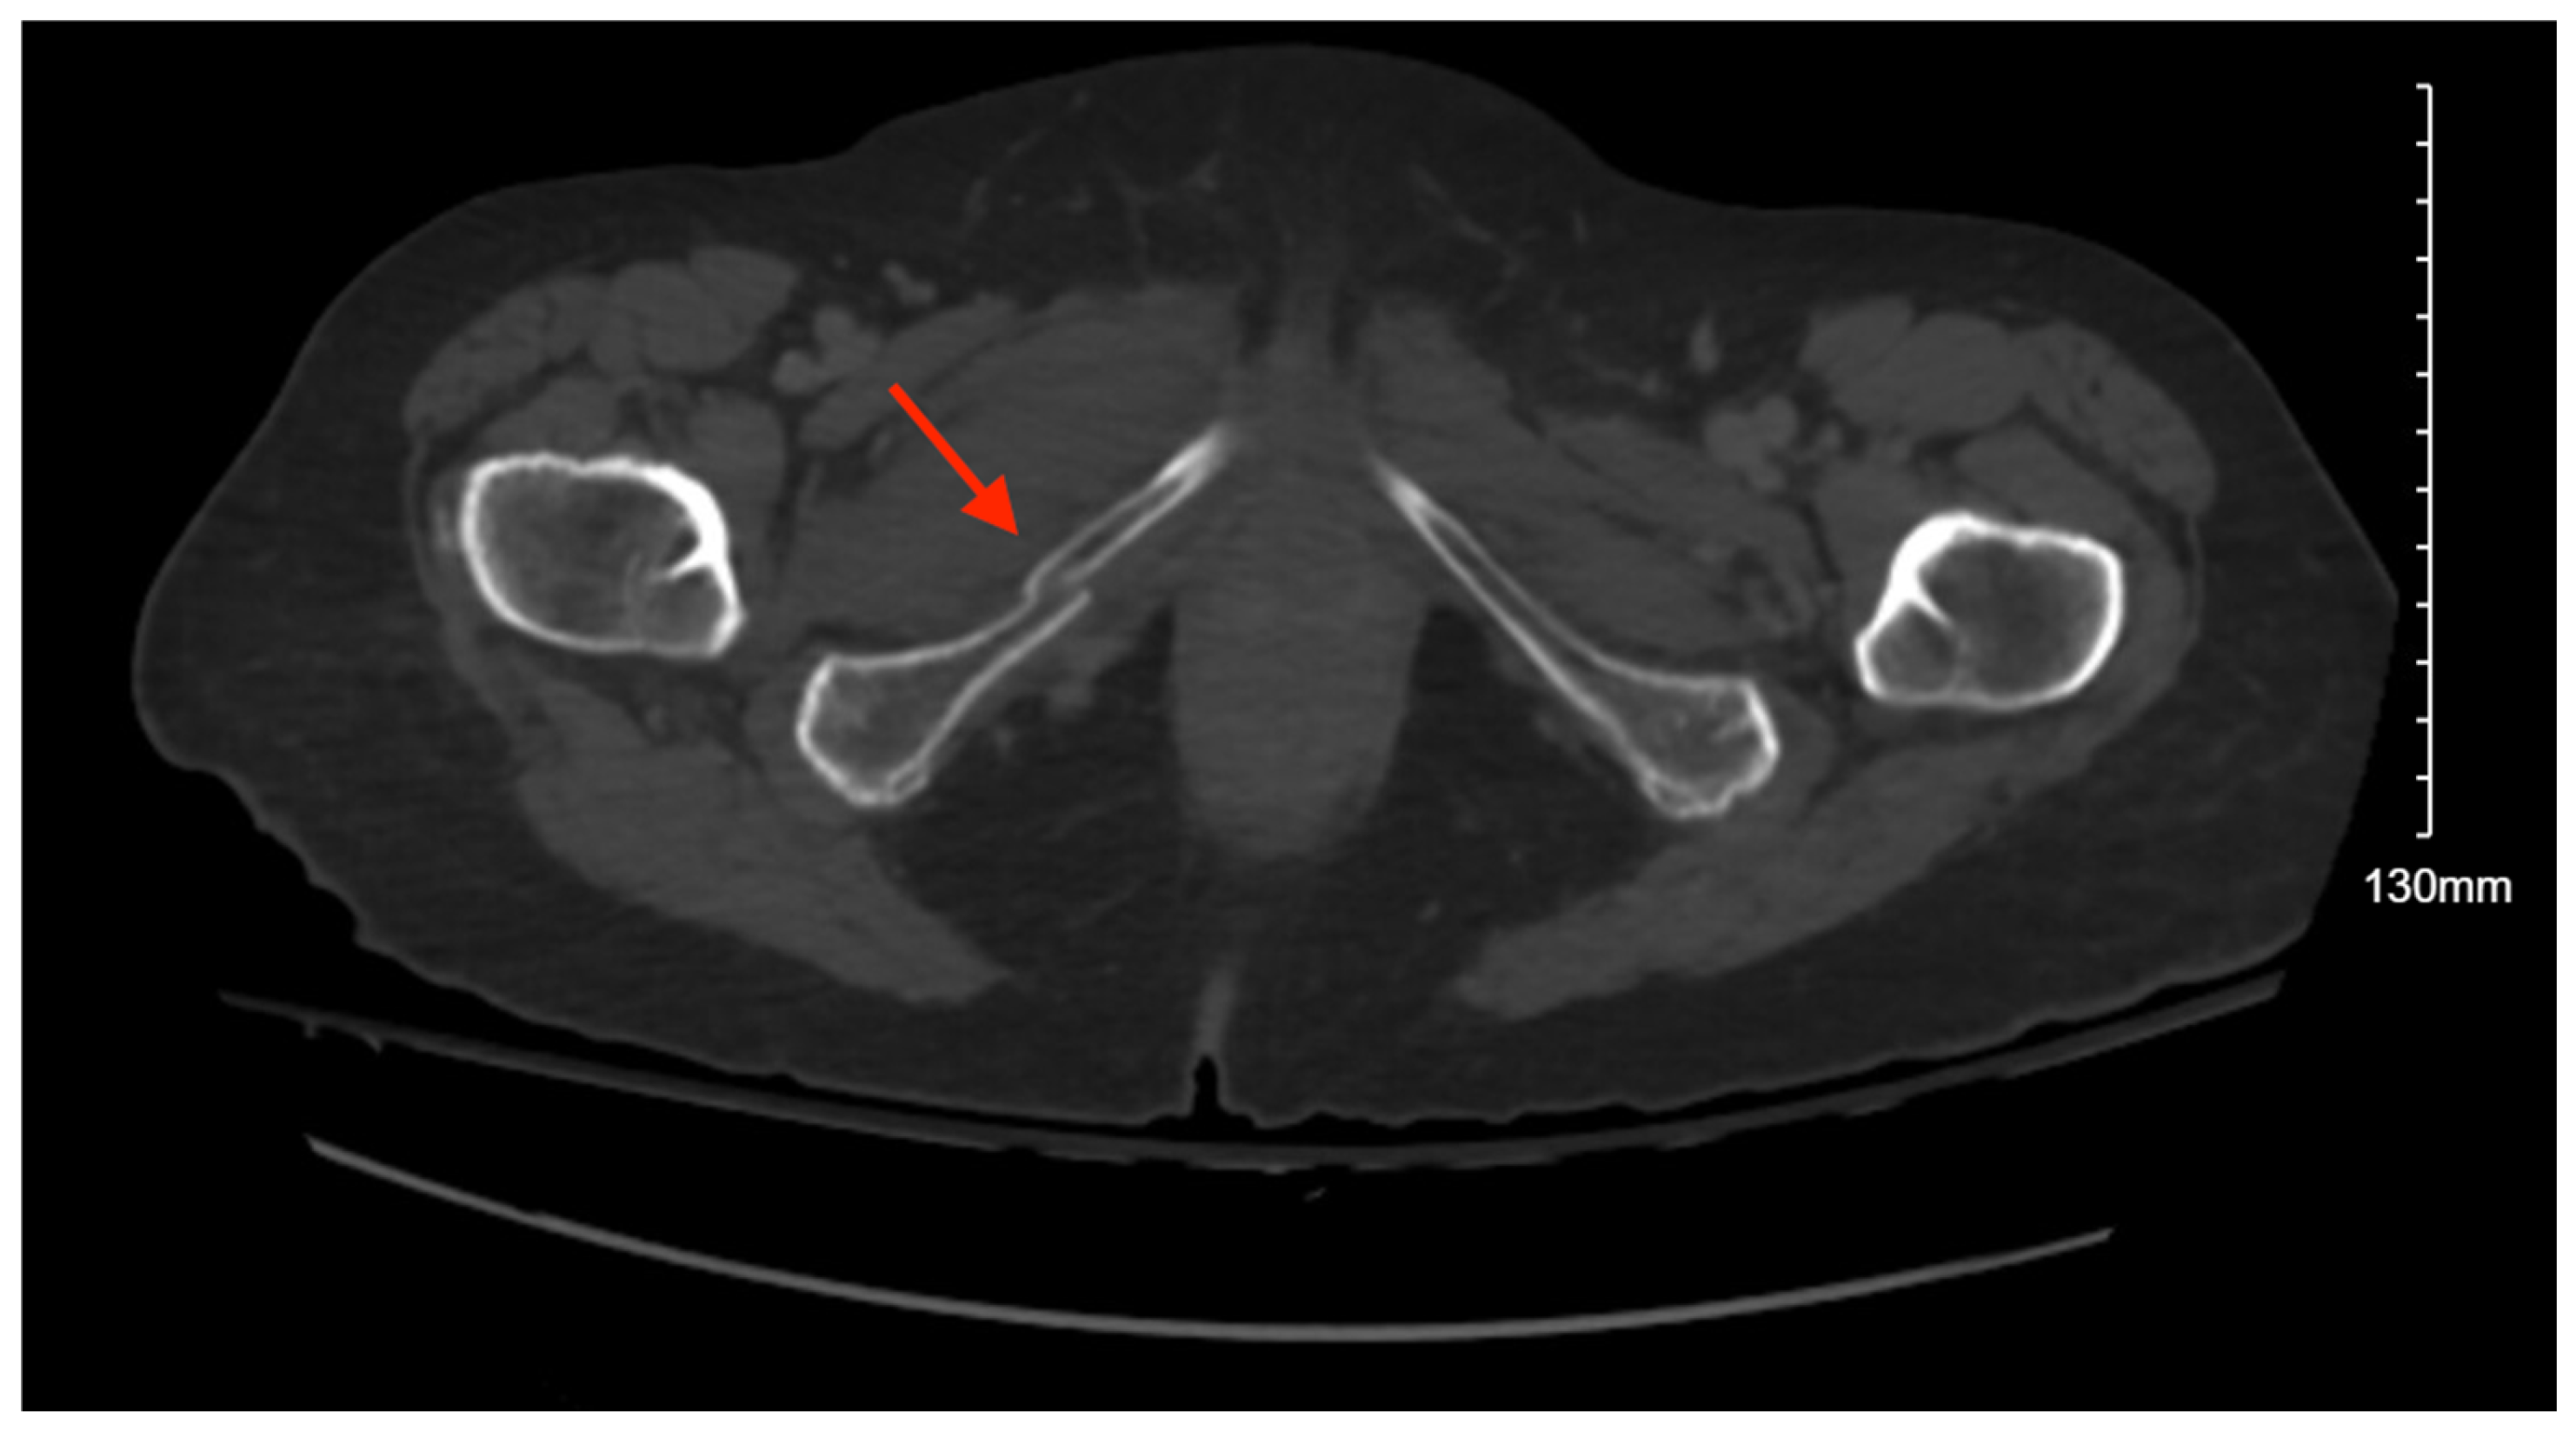

3.10.2. Imaging

Pelvic imaging showed an acute right sacral ala fracture, a nondisplaced acute right inferior pubic ramus fracture, and a nondisplaced acute fracture involving the lateral aspect of the right acetabulum (Figure 10). Additional imaging showed bilateral pneumothoraces, a small right hemothorax, fractures involving the posterior 9th through 12th ribs, grade II hepatic injury, concern for renal contusion, and L1–5 transverse process fractures. There was also retroperitoneal fluid surrounding the upper abdominal aorta without contrast blush and a linear flap within the upper abdominal aorta at the level of the celiac and SMA origins, concerning for traumatic injury.

Figure 10. CT abdomen/pelvis images of the described fractures in case 10. Red arrows are used to indicate the location of pelvic fractures for easier identification.